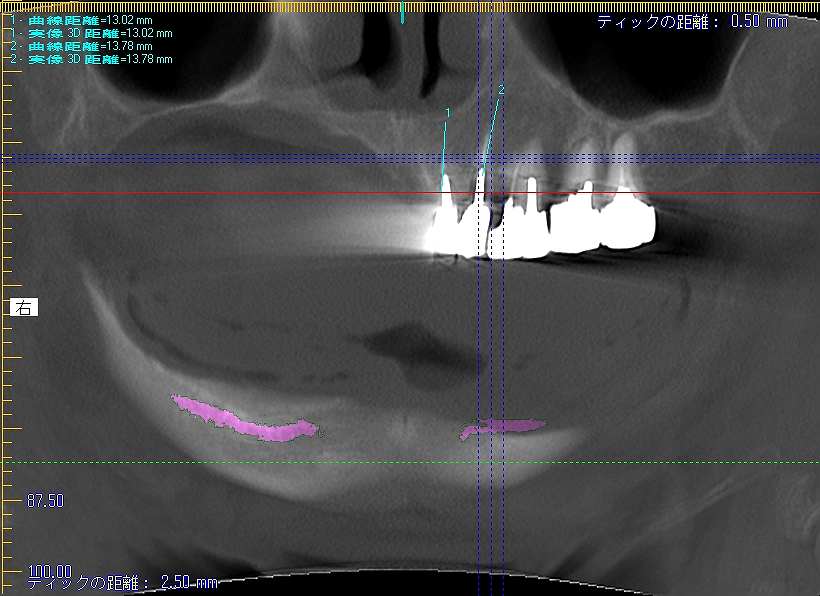

右上は大きく顎堤が無くなっていました

かなりの吸収量です

残存歯になります

下顎も入れ歯を使用していますが、、、

大きな吸収量です

術前のパノラマになります